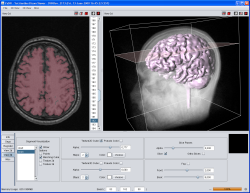

Screenshots

|

|

|

| YaDiV Hauptfenster | Region of Interest | Segmentierung |

|

|

|

| 2D Segmentvisualierung | 3D Segmentvisualierung | Marching Cube |